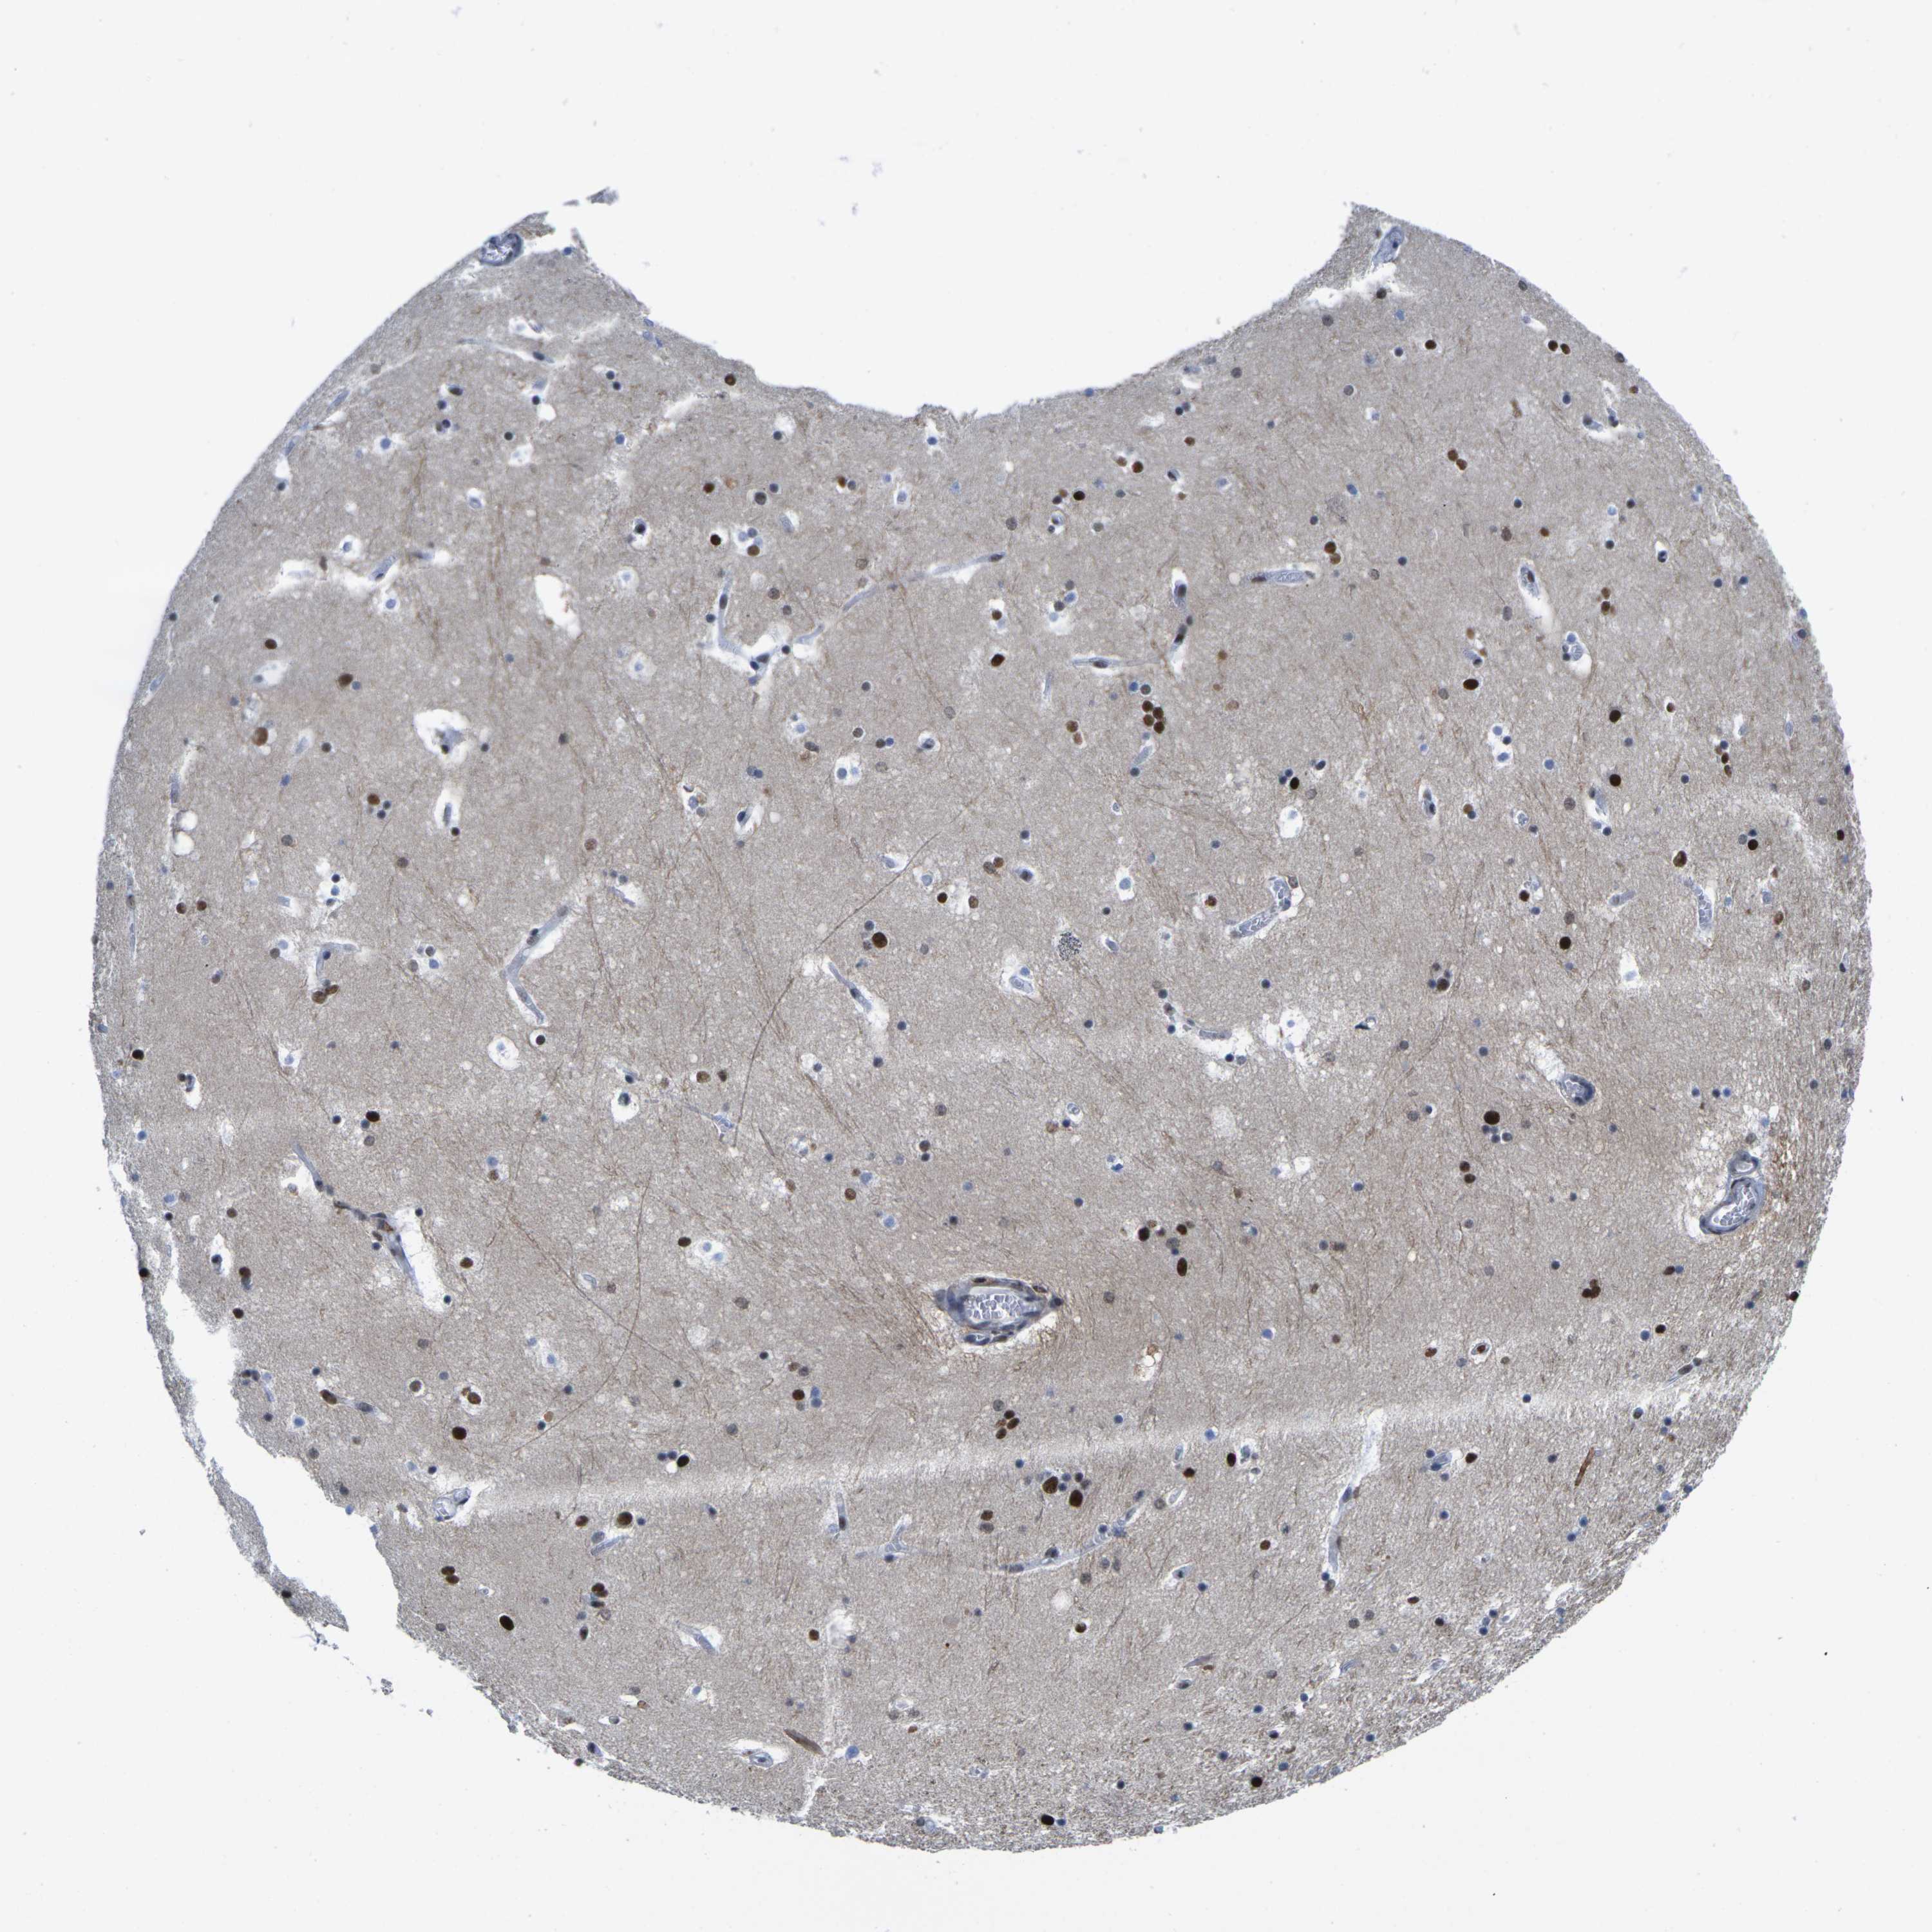

Antibody staining in the annotated cell types in the current human tissue is reported as not detected, low, medium, or high. This score is based on the staining intensity and fraction of stained cells.